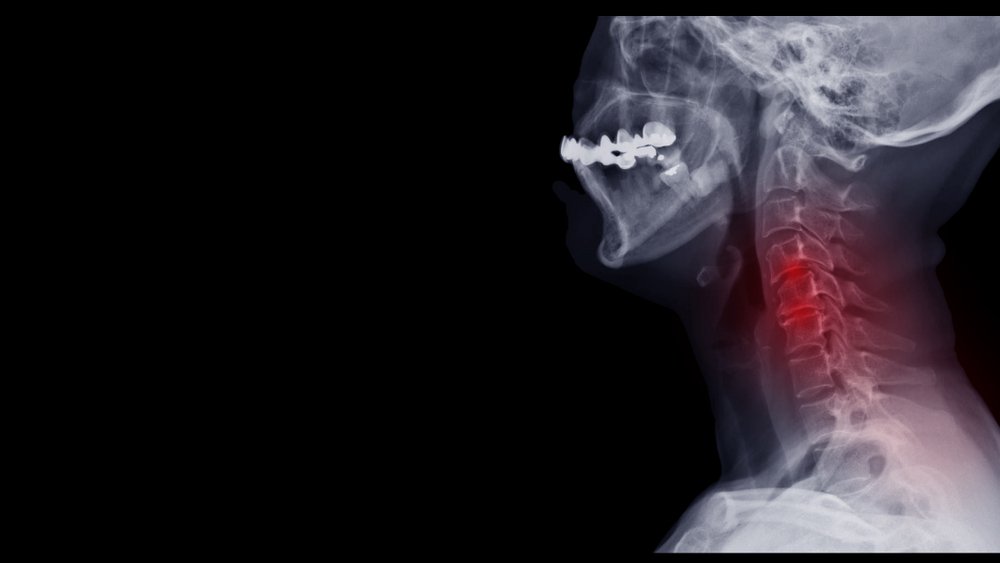

신경근병증은 척추의 신경이 눌리는 것입니다. 마모나 손상으로 인한 주변 뼈와 연골의 변화로 발생합니다. 이러한 변화는 신경근에 압력을 가할 수 있습니다. 신경근은 척수에서 나와 척추의 구멍을 통과하는 각 척수 신경의 일부입니다. 신경근의 만성적 손상으로 인해 말초에 통증이 발생하는 것을 신경근병증이라 합니다.

신경근병증을 진단하기 위해 의사는 먼저 신체 검사를 수행합니다. 그런 다음 영상검사를 실시할 수 있는데, 엑스레이 검사를 통해 디스크의 뼈 정렬 또는 협착을 보고, MRI촬영을 통해 연조직, 척수 및 신경근을 확인하며, CT촬영을 통해 뼈 박차를포함한 뼈의 미세 세부 사항을 확인할 수 있습니다. 또한, 근전도 검사를 실시할 수 있는데, 이 근전도 검사는 의사가 손상 정도나 위치를 식별하는 데 도움이 되는 휴식과 수축 중에 근육의 전기 자극을 측정합니다.